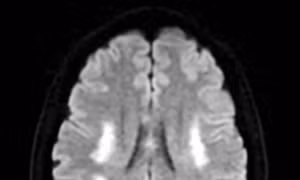

Bác sĩ điều trị cho bà L..